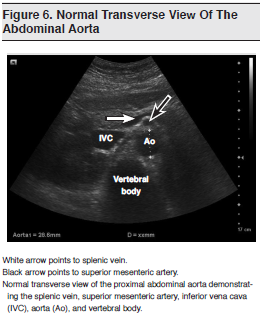

In many ways, ultrasound is the ideal tool for diagnosing AAAs. (See Figures 6 and 7.) It offers the same benefits as for other applications, in that it is rapid, accurate, noninvasive, inexpensive, and reproducible; it involves nonionizing radiation; and it can be done at the patient’s bedside. This is particularly important in the unstable hypotensive patient who cannot travel to the CT scanner. The use of ultrasound to assess for AAAs was described in the literature as early as 1977. Goldberg described its use in detecting a normal aorta or an AAA and in defining the anatomy and extent of disease.51 Since then, there has been considerable research on the role of bedside ultrasound in the assessment of AAAs.